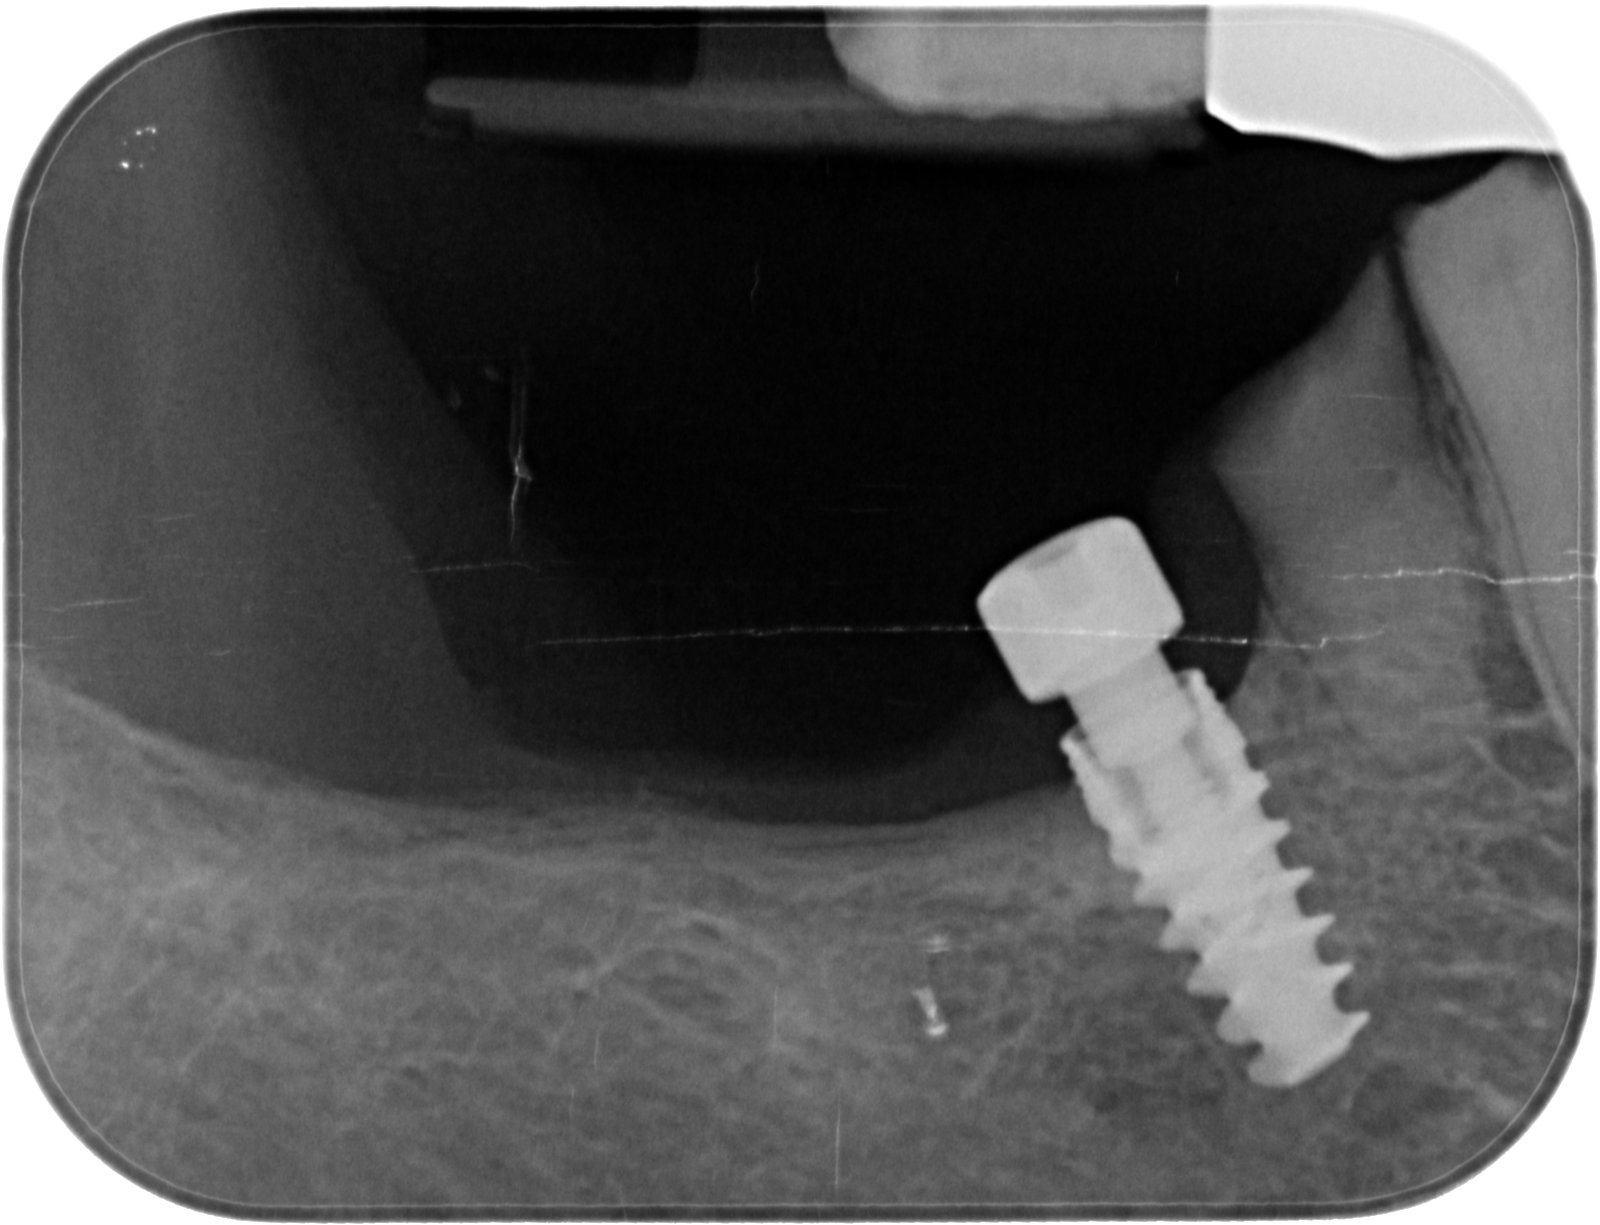

Buenas tengo está paciente que viene de iDental. El implante del 26 es conecxio externa universal, así que no hay problemas. La cosa está en el 24 que es un [...]

Buenas compañeros , me podriais ayudar con la marca de este implante? 1 saludo y muchas gracias